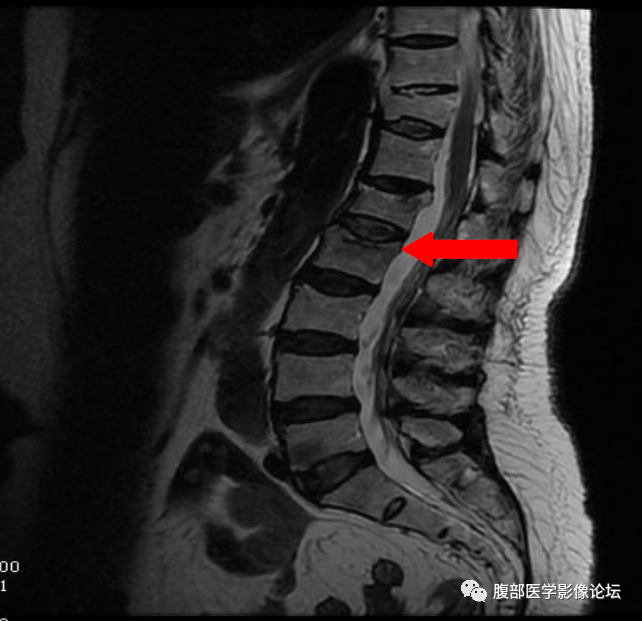

骨质疏松型压缩性骨折?

发生误诊,只是片面的看到了椎体在抑脂像呈高信号,而没有从细节方面着手。

1、T1WI 椎体内脂肪残留程度

良性骨折:椎体内至少残留部分脂肪成分(正常黄骨髓部分残留) 恶性骨折:椎体内黄骨髓被肿瘤组织完全取代,椎体脂肪信号完全消失。

椎体良性与恶性骨折的鉴别其实还有一些鉴别点,但是笔者认为上面六点是最主要的,同时需要指出,任何单独一个鉴别点都不是绝对的,就拿本例来说,仔细看,T1WI 系列还是可以看到一小部分黄骨髓的,但是椎弓根有受累,又是老年人,我们要想到转移瘤的可能,所以我们要仔细阅片,避免不必要的医疗纠纷。